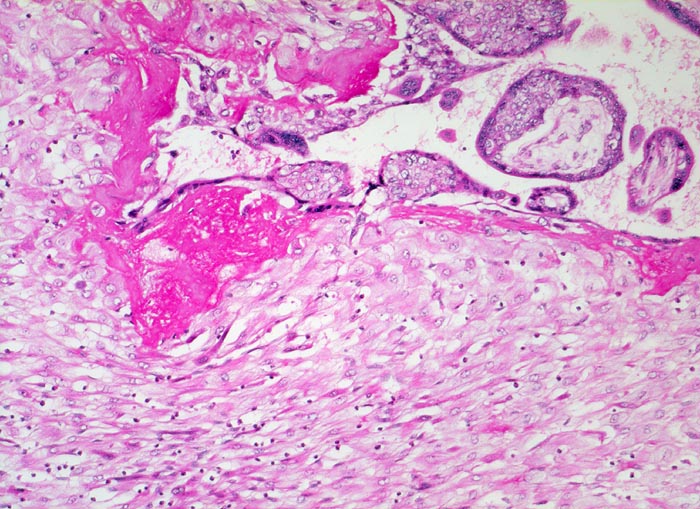

Morphologische Merkmale:

• Myometrium bedeckt von dezidualisiertem Endometriumstroma der Dezidua basalis.

• Invasion des Myometriums durch intermediären extravillösen Trophoblast.

• Fibrinoidschicht.

• Chorionzotten, ein Teil davon verankert mit dem dezidual transformierten Endometrium = Dezidua basalis (Haftzotten).

• Choriondeckplatte.

• Rechts oben Anteile des Chorion laeve.